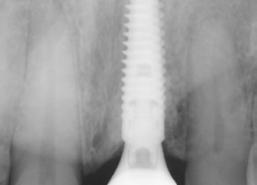

8. Periapical radiograph at 16 months postoperative demonstrating stable crestal bone levels.